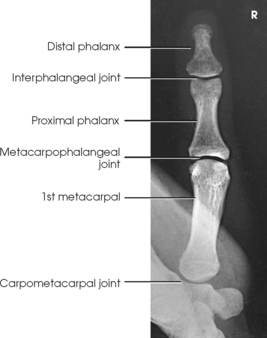

The digits contain 14 phalanges (phalanx, singular), which are long bones that consist of a cylindric body and articular ends. Nine phalanges have two articular ends. The first digit has two phalanges—the proximal and distal. The other digits have three phalanges—the proximal, middle, and distal. The proximal phalanges are the closest to the palm, and the distal phalanges are the farthest from the palm. The distal phalanges are small and flattened, with a roughened rim around their distal anterior end; this gives them a spatulalike appearance. Each phalanx has a head, body, and base.

Five metacarpals, which are cylindric in shape and slightly concave anteriorly, form the palm of the hand (see Fig. 4-1). They are long bones consisting of a body and two articular ends—the head distally and the base proximally. The area below the head is the neck where fractures often occur. The first metacarpal contains two small sesamoid bones on its palmar aspect below the neck (see Fig. 4-1). A single sesamoid is often seen at this same level on the second metacarpal. The metacarpal heads, commonly known as the knuckles, are visible on the dorsal hand in flexion. The metacarpals are also numbered 1 to 5, beginning from the lateral side of the hand.

The interphalangeal (IP) articulations between the phalanges are synovial hinge type and allow only flexion and extension (Fig. 4-8). The IP joints are named by location and are differentiated as either proximal interphalangeal (PIP) or distal interphalangeal (DIP), by the digit number, and by right or left hand (e.g., the PIP articulation of the fourth digit of the left hand) (Fig. 4-9, A and B). Because the first digit has only two phalanges, the joint between the two phalanges is simply called the IP joint.

The metacarpals articulate with the phalanges at their distal ends and the carpals at their proximal ends. The metacarpophalangeal (MCP) articulations are synovial ellipsoidal joints and have the movements of flexion, extension, abduction, adduction, and circumduction. Because of the less convex and wider surface of the MCP joint of the thumb, only limited abduction and adduction are possible.

The carpals articulate with each other, the metacarpals, and the radius of the forearm. In the carpometacarpal (CMC) articulations, the first metacarpal and trapezium form a synovial saddle joint, which permits the thumb to oppose the fingers (touch the fingertips). The articulations between the second, third, fourth, and fifth metacarpals and the trapezoid, capitate, and hamate form synovial gliding joints. The intercarpal articulations are also synovial gliding joints. The articulations between the lunate and scaphoid form a gliding joint. The radiocarpal articulation is a synovial ellipsoidal type. This joint is formed by the articulation of the scaphoid, lunate, and triquetrum, with the radius and the articular disk just distal to the ulna (Fig. 4-9, C).